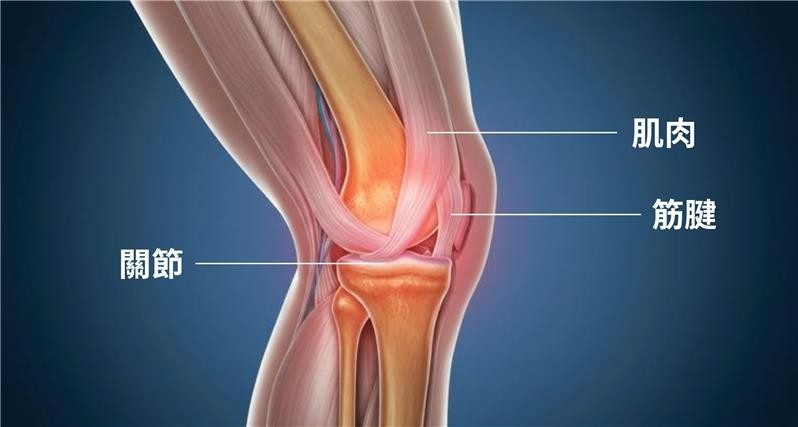

為何「筋」才是關鍵?

「筋」是指肌腱、韌帶、筋膜等軟組織,是關節的第一道防線,它連接人體骨骼與肌肉,負責穩定關節、傳遞力量,讓動作保持流暢。當筋腱出現問題,例如僵硬或鬆弛,關節活動度會下降,甚至伴隨拉扯感,令日常動作變得困難,甚至產生疼痛。尤其在冬季,氣溫低會令血液循環減慢,筋腱彈性下降。關節僵硬,疼痛感更明顯,肩膀、膝蓋等部位更容易繃緊酸痛。要紓緩關節問題必先從「強筋」着手,讓筋與關節更順暢協調運作,達至強筋止痛。